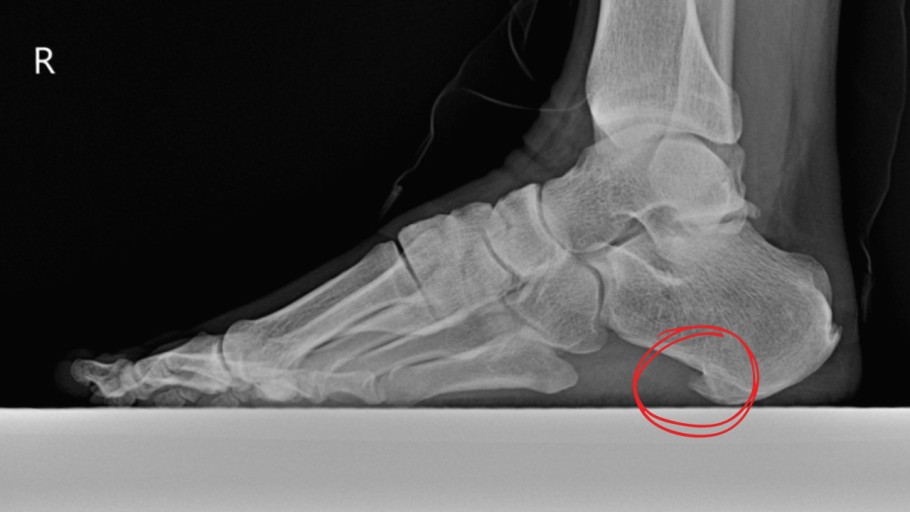

초기에는 밤에만 불편함을 느끼다가 점점 지속 시간도 늘어납니다.3. 족저근막염

발바닥 통증의 대표 질환으로,

발뒤꿈치에서 발바닥 전체로 이어지는 근막에 염증이 생기며

걷거나 서 있을 때 발바닥이 뜨겁고 찌릿한 통증을 유발합니다.

특히 아침에 첫 발을 디딜 때 더 아픈 경우가 많아요.